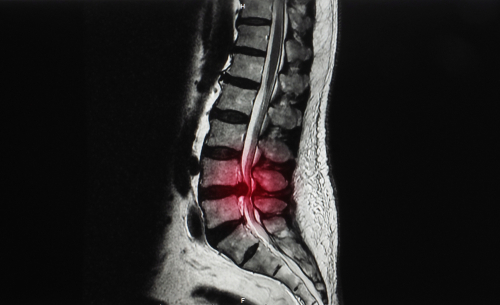

Degenerative Disc Disease (DDD) is a lower back (lumbar) or neck (cervical) condition. It affects the discs located in between the vertebrae of the spine. ‘Degenerative’ is used to describe the condition of the intervertebral disc(s) affected. Degenerative disc disease is not actually a disease. It is a natural process by which the intervertebral discs of the spine change over time. This condition describes damage to the spinal discs resulting in pain through the neck or lower back, often with associated pain radiating down the arms or legs. Patients suffering from this condition often experience low-level chronic pain broken up by intermittent episodes of acute pain that can be severe and disabling.

The risk of DDD increases with age. At birth, water makes up 80 percent of the discs. As we age, the discs in our spine lose water and elasticity and they do not absorb shock and movement as well as they did earlier in life. Arthritis and osteoarthritis can also contribute to its onset by placing greater pressure on the discs, increasing the risk of a rupture. Risk factors for degenerative disc disease include age, obesity, lack of exercise, trauma, family history, osteoporosis, and smoking. Sudden, acute injuries such as a fall may cause the outer layer of the disc to tear or crack, causing it to bulge, rupture or fragment. Once this has occurred, motion amongst the vertebrae can cause tension and irritation in the surrounding muscles, joints and nerves.